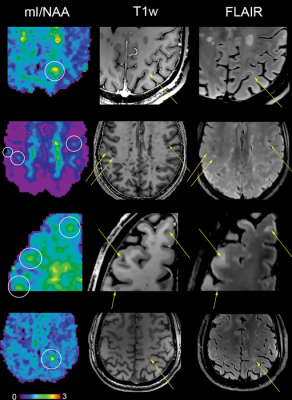

Metabolic maps showing the ratio of myo-inositol to N-acetylaspartate (mI/NAA) clearly depict small subcortical or juxtacortical lesions (circles) that appear inconspicuous at T1-weighted MRI (T1w)/fluid-attenuated inversion-recovery (FLAIR) imaging (indicated with arrows in three participants with multiple sclerosis). Image courtesy of Radiological Society of North America

Lesions to the brain’s signal-carrying white matter are the most readily detectable manifestation of MS on MRI. The lesions, linked to the loss of the protective coating around white matter fibers called myelin, represent only macroscopic tissue damage. A means to find changes in the brain at an earlier microscopic or biochemical stage would be beneficial.

The results showed reduced levels of an amino acid derivative called N-acetylaspartate (NAA) in patients with MS. Lower levels of NAA have been linked to impaired integrity of neurons in the brain. People with MS also showed elevated levels of myo-inositol (MI), a compound involved in cell signaling. Higher levels are indicative of substantial inflammatory disease activity.

The metabolic alterations in normal-appearing white matter and cortical gray matter were associated with disability.

“MRI of neurochemicals enables the detection of changes in the brain of multiple sclerosis patients in regions that appear inconspicuous on conventional MRI,” said study senior author Wolfgang Bogner, Ph.D., from the High Field MR Centre at the Medical University of Vienna in Vienna, Austria. “The visualized changes in neurochemistry of normal-appearing brain tissue correlated with the patients’ disabilities.”